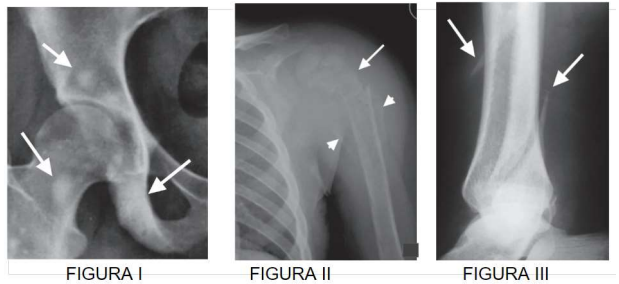

Analise as figuras (I, II e III) e as indicações das setas, depois assinale a alternativa correta.